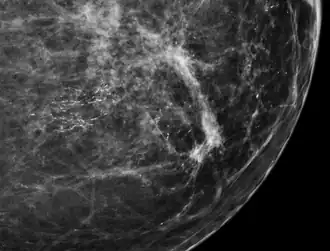

-

Mammogram microcalcifications in ductal carcinoma in situ -

DCIS has been classified according to the architectural pattern of the cells (solid, cribriform, papillary, and micropapillary), tumor grade (high, intermediate, and low grade), or the presence or absence of comedo histology;[8] or, in the case of the apocrine cell-based in situ carcinoma, apocrine ductal carcinoma in situ, it may be classified according to the cell type forming the lesion.[9] DCIS can be detected on mammograms by examining tiny specks of calcium known as microcalcifications. Since suspicious groups of microcalcifications can appear even in the absence of DCIS, a biopsy may be necessary for diagnosis.

80% of cases in the United States are detected by mammography screening.[23] More definitive diagnosis is made by breast biopsy for histopathology.